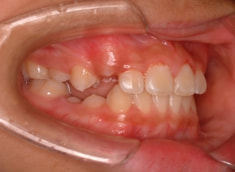

治療前

治療開始時

治療分析:日本人の反対咬合や下顎前突は、上顎の劣成長を伴なうことがほとんどで、本ケースも上顎劣成長でしたので、上顎を側方拡大と前方に牽引しました。側方拡大方法は急速拡大で正中口蓋縫合の拡大を行い、同時に横口蓋縫合を剥がす効果があり、前方牽引の効果を促進します。

日本人の典型的なパターンである、上顎劣成長が顕著で、下顎骨体自体も大きめです。